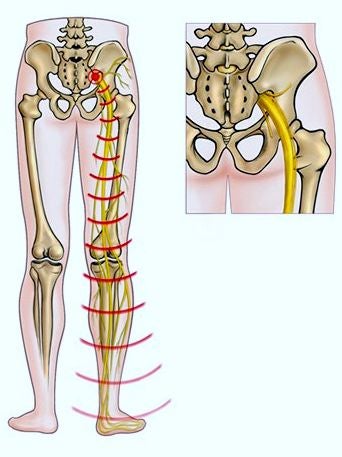

Dat een hernia zo loopt langs je benen